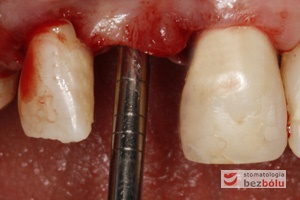

Procedura zachowania równoległości – w odniesieniu do osteotomu pierwszy nawiert dla drugiego implantu wykonywany jest paralelnie

Osteotomy symultanicznie wprowadzone do łoży implantów – dbałość o równoległość implantów względem osi własnych i zębów sąsiednich

Ocena pozycji implantów w wymiarze strzałkowym – piny do oceny równoległości wprowadzone do łoży implantów – widok okluzyjny